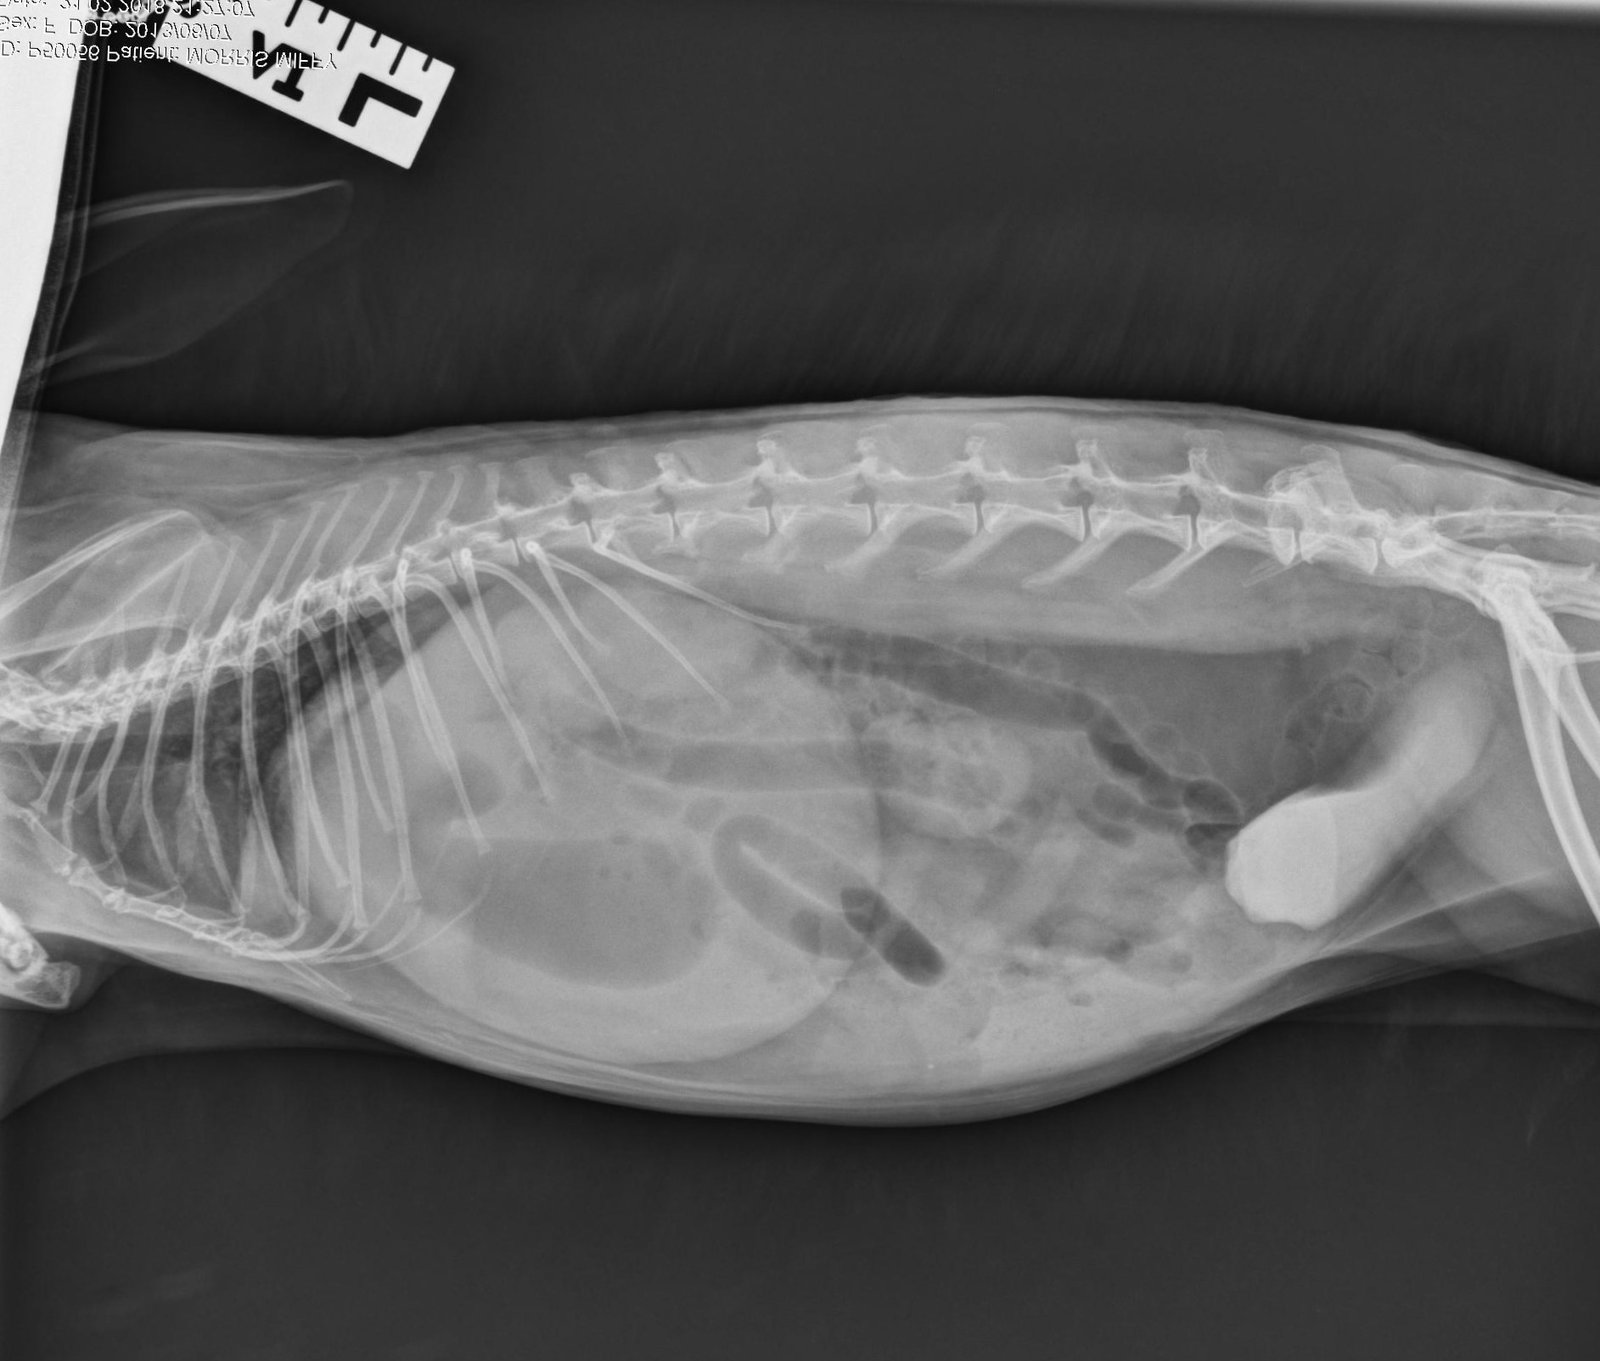

Photo reference: